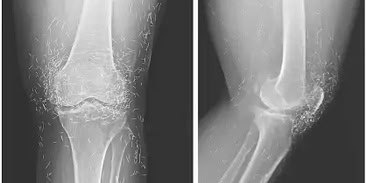

В Южной Корее у 65-летней женщины с остеоартритом в коленном суставе нашли… золотые нити.

✨ Всё оказалось проще, чем алхимия: долгие годы она лечила сустав иглоукалыванием с использованием золотых нитей. На рентгене это выглядело как россыпь частиц вокруг колена — сотни блестящих «осколков».